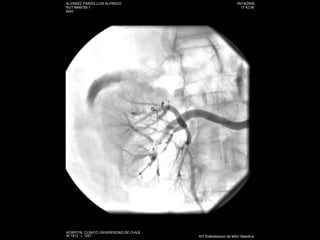

Angiografía

Estudio No invasivo: AngioTC Doppler Angio RM:  esclerosis sistémica  nefrogénica Invasivo: angiografía